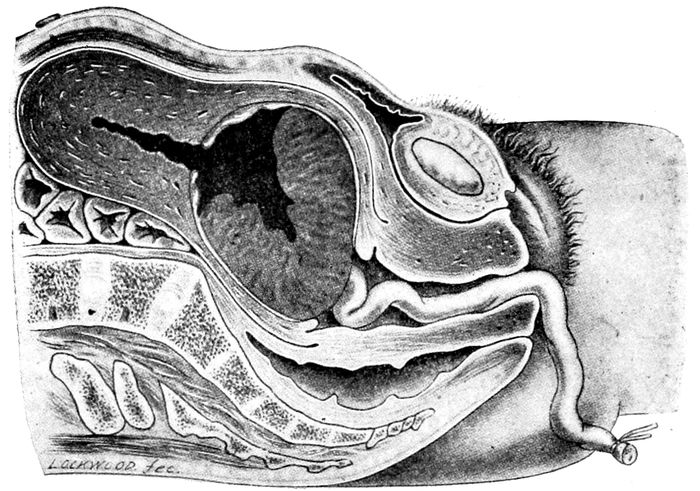

Fig. 3.—Visceral relations. (Redrawn from Gray.)

Inside the pelvis are the organs of generation with

21Of first importance are the ovaries, tubes and uterus,

the true genital organs. They are bounded in front by

viscera, and surrounded everywhere by muscular,

aid their function.